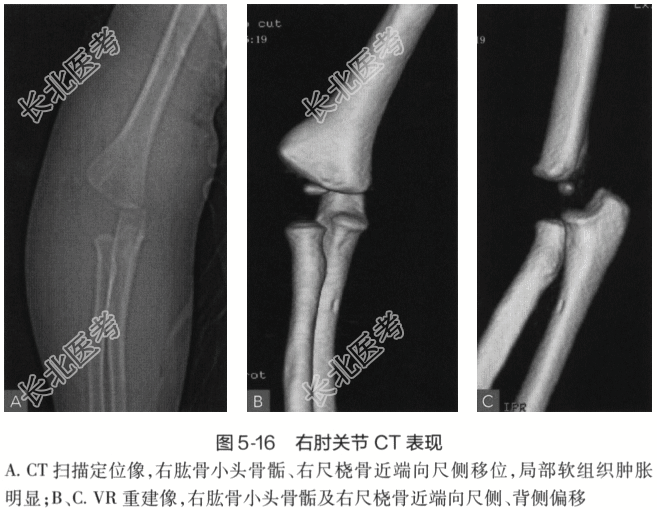

- [材料题] 患者,男性,15个月。右肘关节创伤后肿胀伴活动消失6小时余。外院X线片报告:右肘关节诸骨未见明显骨折征象,未见明显脱位。影像学检查: